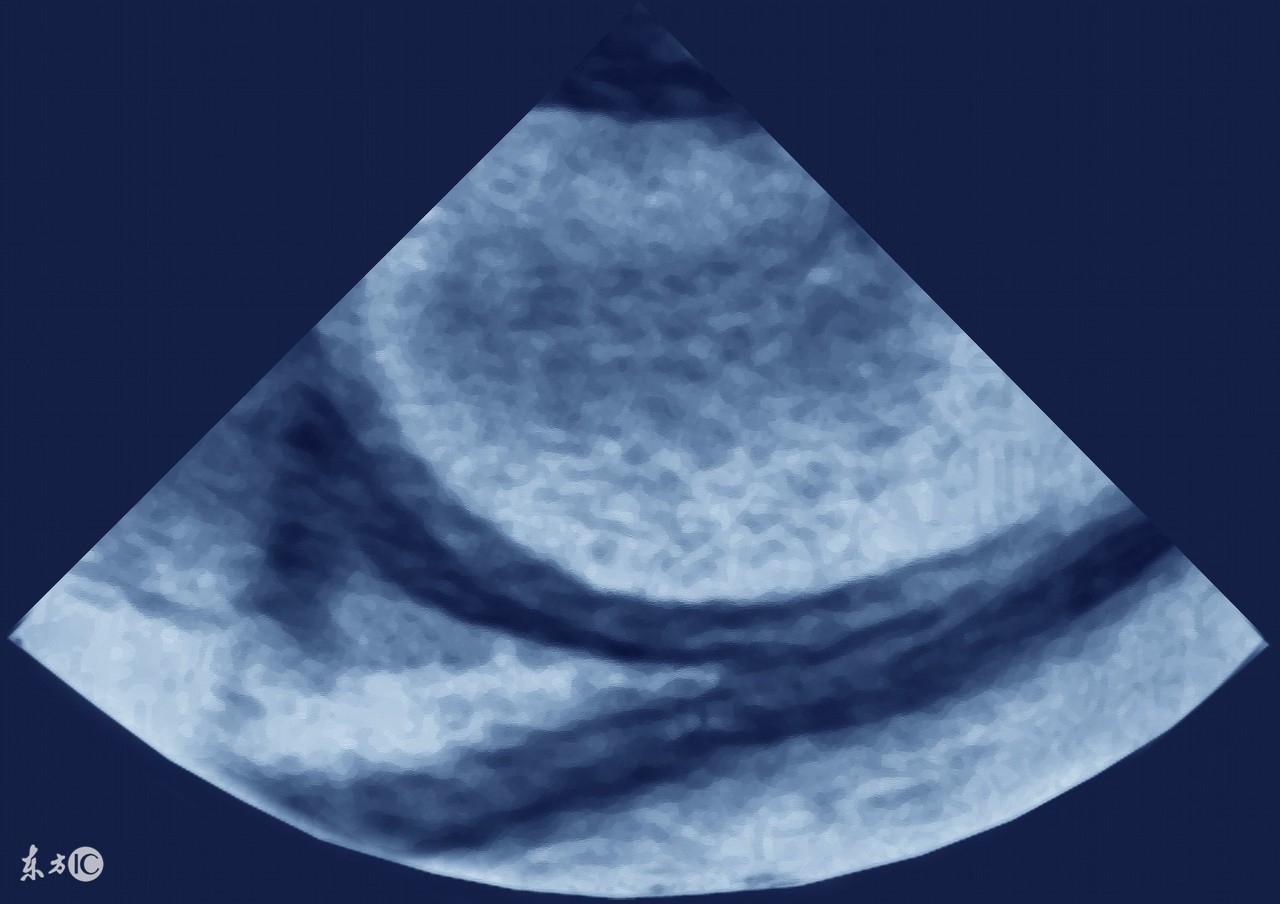

借此机会,就来和大家说一说哪些癌症会引起腹水,因为有不少病人是因为发现肚子鼓鼓的,做B超一看,肚子里有水(腹水),于是找原因,是什么原因引起的腹水?

3、卵巢癌,包括输卵管癌、原发性腹膜癌,这三种癌症的治疗原则是一样的,这类癌症也是引起腹水的最常见原因之一,女性如果有大量的腹水,要首先排除卵巢癌可能,有针对性的重点查一查卵巢输卵管。